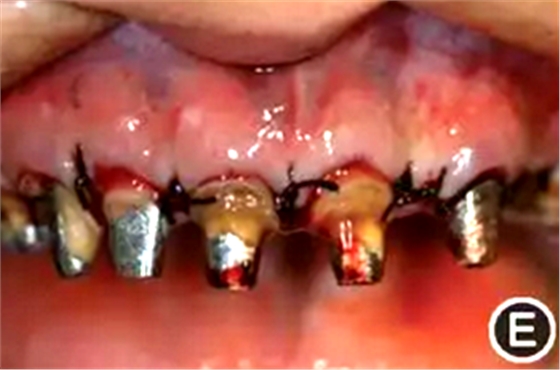

術(shù)后2周進行重新牙體預(yù)備,制作并戴入臨時修復(fù)體,牙齦塑形(圖6)。術(shù)后3個月,上前牙牙齦形、線、點位置基本穩(wěn)定,進行永久修復(fù)。上頜采用烤瓷固定橋修復(fù),樁核冠單冠修復(fù),下頜固定-活動義齒修復(fù),恢復(fù)良好的牙齒外形和接觸區(qū)、重建完整牙列、恢復(fù)口腔功能、改善美學(xué)效果(圖7)。

圖6 臨時冠修復(fù) A:牙冠延長術(shù)后2周,牙齦健康,齦緣位置及形態(tài)協(xié)調(diào);B:臨時冠修復(fù)后即刻